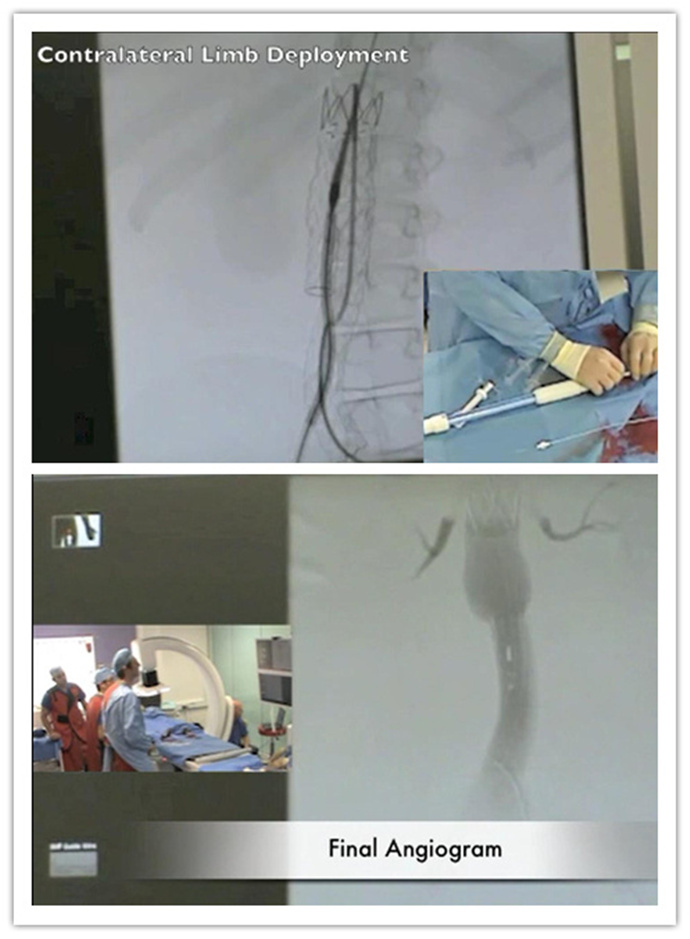

英国帝国理工学院

手术过程视频请点击(请在wifi情况下观看)